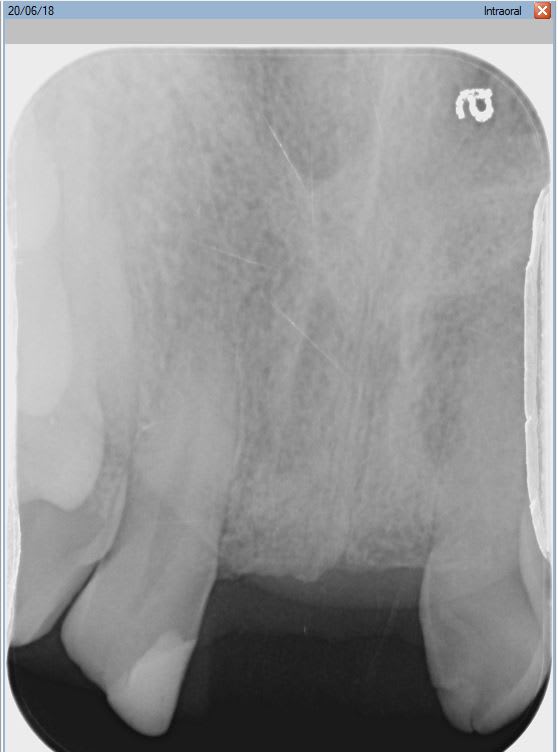

Petit probleme, et alors que pourtant le stellite ne le laisse pas trop deviner (les dents sont legerement vestibulees et esthtiquement, elles rendent assez bien, pas trop petites) ; la distance entre 12 et 22 est reduite.

il n'y a en effet que 12 mm au collet d'une laterale jusqu'au collet de l'autre, et 14.5mm du bord mesial de l'une au bord mesial de l'autre.

Mettre deux implants dans ce cas me semble contre indique... Mes plus petits implants font 3.75 et ne permettront sans doute pas de conserver une distance dent-implant et implant implant suffisante optimale.